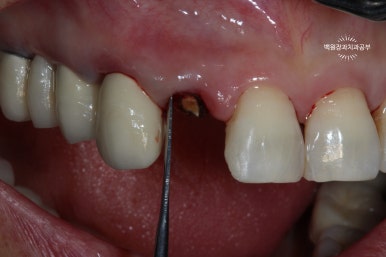

왼쪽: periotome을 사용하여 발치 시행, 오른쪽: 치아를 완전히 뽑지 않고 위치를 수정.

이를 위해 제가 있었던 치주과에서는 페리오톰(periotome)이라는 아~주 얇은 기구를 사용하여 치아를 주변 치조골에서 분리해내어 조심스럽게 약간 빼어내곤 했습니다.

치아를 약간 정출시킨 후 봉합사를 이용하여 고정해줍니다.

보시는 바와 같이 치아를 약간 정출시켜줍니다. 대개는 2-3mm 정도 정출시킵니다.

그렇기 때문에 뿌리가 너무 짧은 치아는 이러한 외과적 정출술이 불가능합니다.